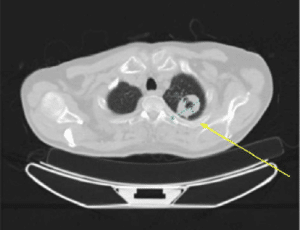

He also had a positron emission tomography (PET)-CT, which was significant for a left apical lung mass with central cavitation despite lack of flurodeoxyglucose (FDG) avidity, suspicious for primary pulmonary malignancy without any anatomic/metabolic, mediastinal/thoracic adenopathy or widespread metastatic disease.

Figure 2: 4.0 x 3.2 cm left apical lung mass with central cavitation, with lack of FDG avidity